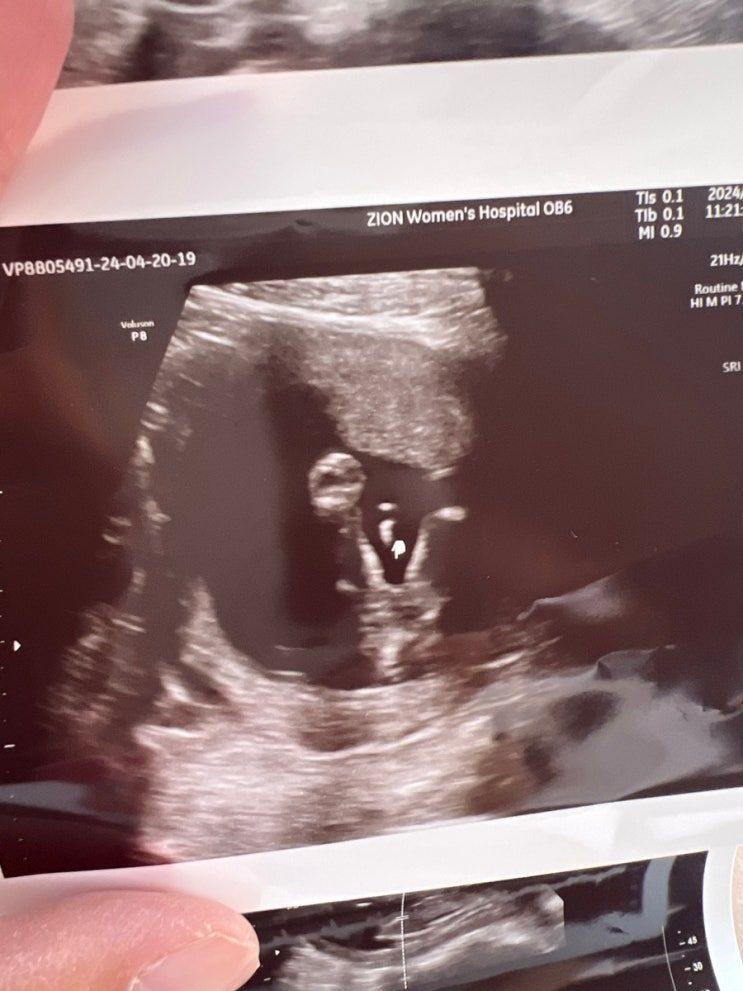

[둘째 임신일기] 26주차 - 32주차 크기.증상 (임신 축하선물/아기초음파)

26주차엔 귀여운 양배추 크기가 되었다!! 둘째 임신이라 주변사람들에게 많이 알리진 않았다. 그래도 아시...